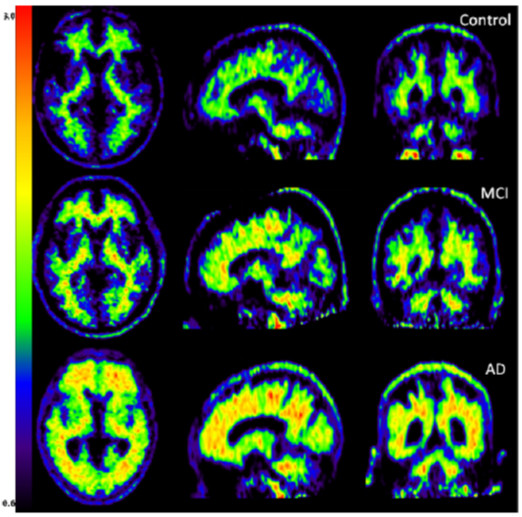

Le rôle "complice" de la protéine Tau est suspecté. Une étude récente par imagerie TEP utilisant un agent de contraste semble le vérifier.

Le rôle "complice" de la protéine Tau est donc suspecté. Une étude récente par imagerie TEP utilisant un agent de contraste semble le vérifier.

Les progrès rapides et considérables de l'imagerie (en particulier fonctionnelle), permettent de diagnostiquer les lésions cérébrales -dont la maladie d'Alzheimer- à des stades de plus en plus précoces.

La tomographie par émission de positons (TEP ou Pet-Scan) est particulièrement adaptée et performante pour cet usage.